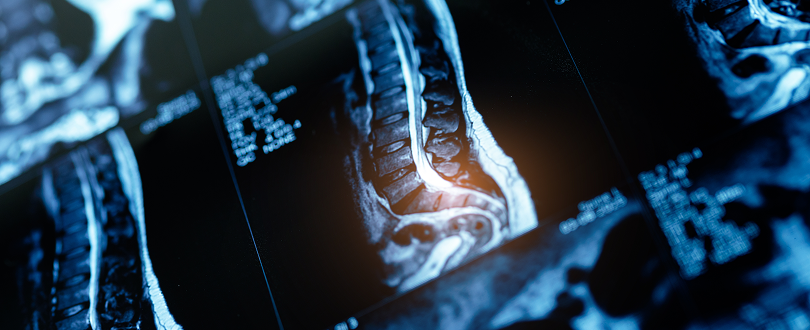

Spinal cord injuries may occur due to severe car accidents or from seemingly minor slip and fall accidents. Anything that causes a sudden and traumatic blow to your spine that fractures or compresses one or more of your vertebrae can leave you with lasting damage.

The spinal cord has protection, but it is still a delicate part of your body. It takes just the right set of circumstances to cause you a life-altering injury. The fact that these injuries can alter your life forever makes them especially tragic. You may end up in a wheelchair, unable to move your limbs, or needing in-home care for the rest of your life.